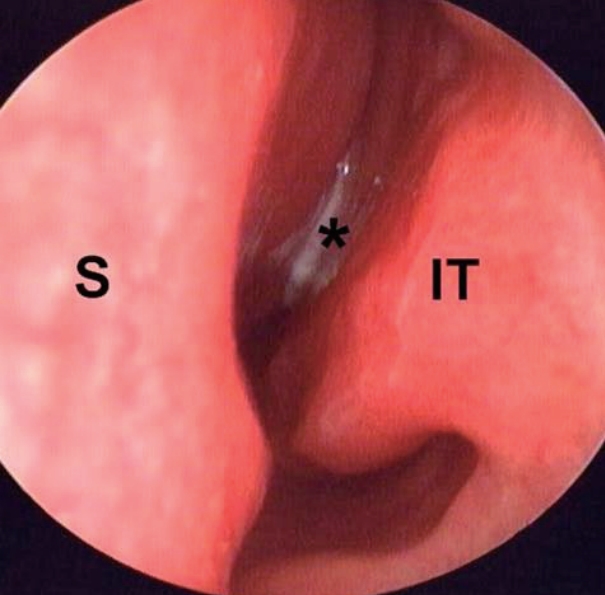

A 67-year-old man was admitted to our clinic with rhinorrhea and nasal obstruction of the left nasal cavity that had developed approximately 1 month ago. He did not have symptoms such as facial pain, swelling, bleeding, or foul odor. There was no underlying disease except allergic rhinitis in his past history. Although he underwent treatment of dental caries in the right lower first molar 6 months ago, there was no history of dental problem in the upper molar area. Endoscopic examination showed a nasal polyp and mucopurulent discharge in the left nasal cavity (Fig. 1). CT of the paranasal sinuses showed soft tissue density and calcification in the left maxillary sinus, which is consistent with signs of a fungal ball (Fig. 2). There was no feature that was suspicious of malignancy, such as destruction and invasion of the surrounding structures. Endoscopic sinus surgery was planned under local anesthesia for histopathologic diagnosis and treatment with the suspicion of a fungal ball.